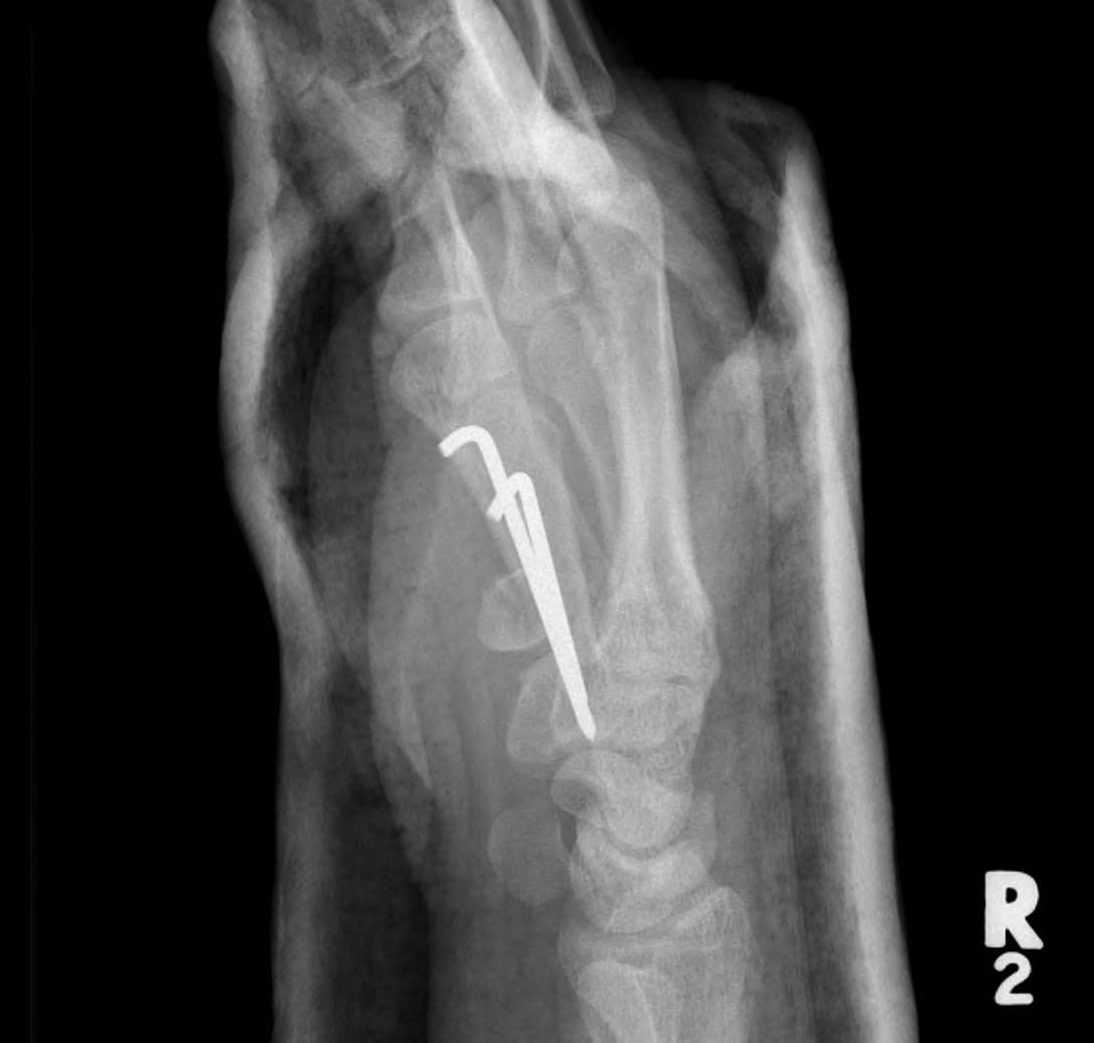

B. Rolando Fracture

Fracture

- 2 small intra-articular fragments

- poor prognosis

Operative management

Indications

Displacement

Technique

Dorsal approach

- protect superficial radial nerves

- between APL / EPB and EPL

- attempt to anatomically reduce and fix with plate